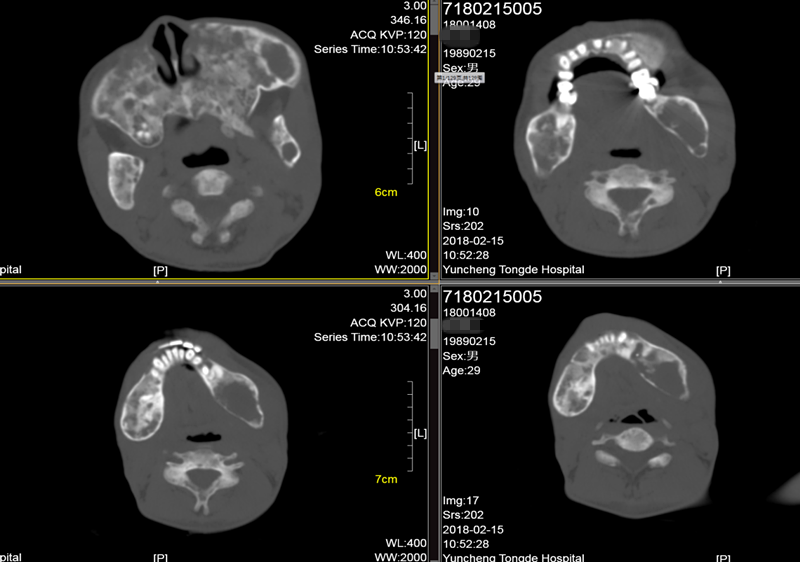

辅助检查:糖化血红蛋白6.2%;甲状旁腺激素87pg/ml(15-65);25-羟维生素D23.63ng/ml(>20) ;血镁0.71mmol/L(0.66-1.07);血钙2.32mmol/L(2.15-2.55) ;血磷0.83mmol/L(0.81-1.45);24小时尿钙3.01nmol/24h(2.5-7.5);24小时尿磷10.9nmol/24h(13-42);TP1NP:1052ng/ml(9.06-72.64);β-CTX :2.68ng/ml(0.043-0.783);骨钙素:255.3ng/ml(24-70);血碱性磷酸酶:691U/L(40-129);血清抗酒石酸酸性磷酸酶:10.3U/L(≤4.47);骨源性碱性磷酸酶:75U/L;人护骨素:110ng/L ;骨密度(DXA):左前臂骨密,Z值-6.9;腰椎骨密度正常;胸腰段正侧位片示:考虑骨纤维异常增殖症伴骨质疏松;颌骨CT示:上颌骨地图样改变,下颌骨囊状空泡、丝瓜瓢状改变,考虑骨纤维异常增殖症;右上肢平片示:囊状膨胀性、丝瓜瓢状改变;胸片:考虑骨纤维异常增殖症。

▼ 颌骨CT示: